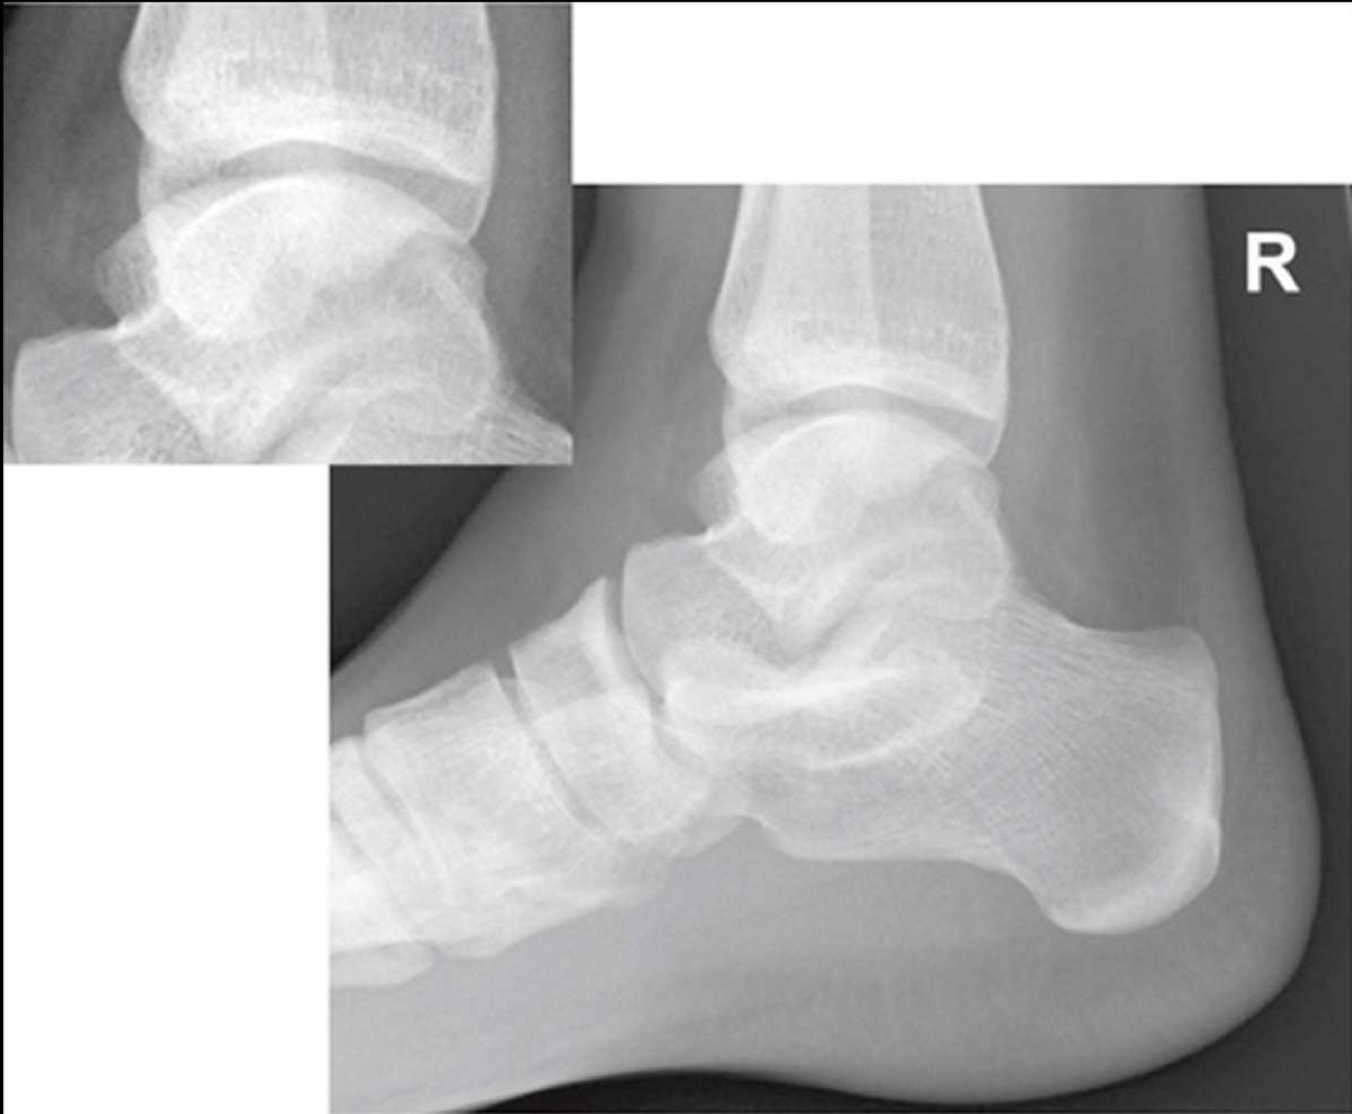

Lateral Ankle

Patient Position

Lying on affected side with lateral ankle against IR

o Can be standing

Part Position

Foot dorsiflexed to place foot at right angle to tib/fib

Affected ankle in a true lateral

Lateral malleolus located 1 cm posterior to the medial malleolus

CR

perpendicular to medial malleolus

Collimation

to include entire ankle joint, distal tib/fib and base of 5th metatarsal

especially the base of the 5th

Evaluation Criteria of lateral ankle

Entire talus and calcaneus visualized

Base of 5th metatarsal demonstrated

Lateral malleolus superimposed over posterior half of tibia

Talar domes superimposed & tibiotalar joint is open

Optimal exposure factors – visualize the distal fibula through the talus.

Should see anterior pretalar and posterior pericapsular fat pads

Note: Foot must be dorsiflexed 90° for anterior pretalar fat pad to properly demonstrated

is this lateral ankle over or under rotated

under